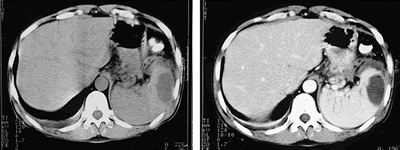

入院后予禁食、抑酸、补液治疗,腹痛渐缓解。逐渐过渡至百普素肠内营养支持,但血P-Amy始终波动在227~776 U/L,多次复查腹部B超和CT(见图),胰尾假性囊肿形成且无明显变化,脾内囊实性占位无明显变化。

图 普通CT扫描及增强扫描均显示脾实质内椭圆形低密度影,

脾门周围、胰周区多个圆形密度减低影,增强后无明显强化。